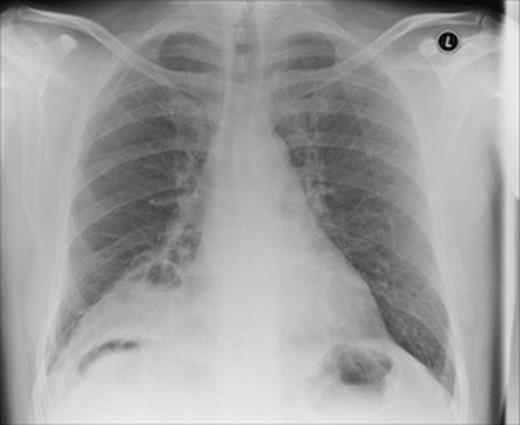

Investigations demonstrated a mildly elevated white blood cell count, with the rest of the blood tests normal. An erect chest x-ray showed an area of increased opacification in the right lower zone, with gas in the right subphrenic space which was reported to be Chilaiditi’s syndrome. (Figure 1)